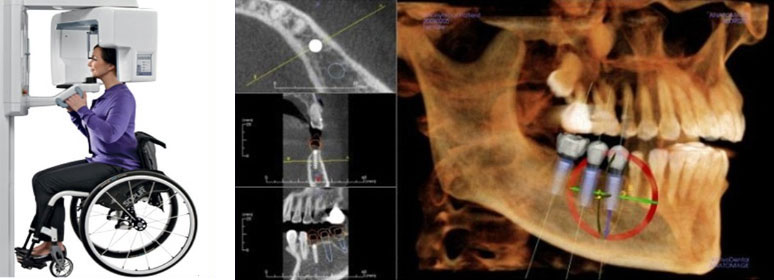

1 通过高智能数字化检查系统扫描得到口腔精准数据,同时兼顾后期修复等诸多因素进行综合考虑,量“齿”定制一种顶级高难度治疗方案——穿颧种植,帮助张阿姨恢复一口好牙! 01 什么是穿颧种植? ![]() 穿颧种植:穿颧种植被称为是当今难度较高的种植技术,指的是颧骨固定种植技术,该技术无论稳定性还是受力性都非常好,也是当今难度较高的种植技术。适用于上颌骨切除、上颌骨重度萎缩、常规内外提升都没有办法达到种植条件的无牙颌患者,通俗地被人称为“无土培栽技术”。 02 为什么说“穿颧种植” 是种植界的“珠穆朗玛峰”? 穿颧手术的关键还是在于患者剩余骨量比较少,需要做一个比较长的颧种植体,植入颧骨区。因为患者牙槽骨严重萎缩,暴露口腔颌骨区域比较少,需要医生对解剖结构比较了解,才能在有限的视野里面成功植入一个比较长的颧种植体。因此,对医生术前设计和术中的操作以及临床经验是一个比较大的考验。 03 穿颧种植和常规种植相比效果如何? 穿颧种植由来已久,国外已经开展多年。综合来看穿颧种植与常规半口全口种植远期的成功率是没有根本区别的,可能只是选择的骨头位置不太一样。在国际上来看,穿颧种植10年里面的成功率大概在97%左右。 1、感觉更舒适,更自然,坚固耐用 2、具有很好的固位效果 3、使咀嚼效率达到与自然牙媲美的程度 4、刺激骨组织,延缓颌骨的吸收与萎缩 5、不损伤邻牙,并且能有效地保护邻牙 ![]() 数字化种植牙技术是将计算机断层扫描技术(CT)、计算机辅助设计技术(CAD)和快速原型制造技术(RP)综合应用于种植手术的放心、准确的方法。 |